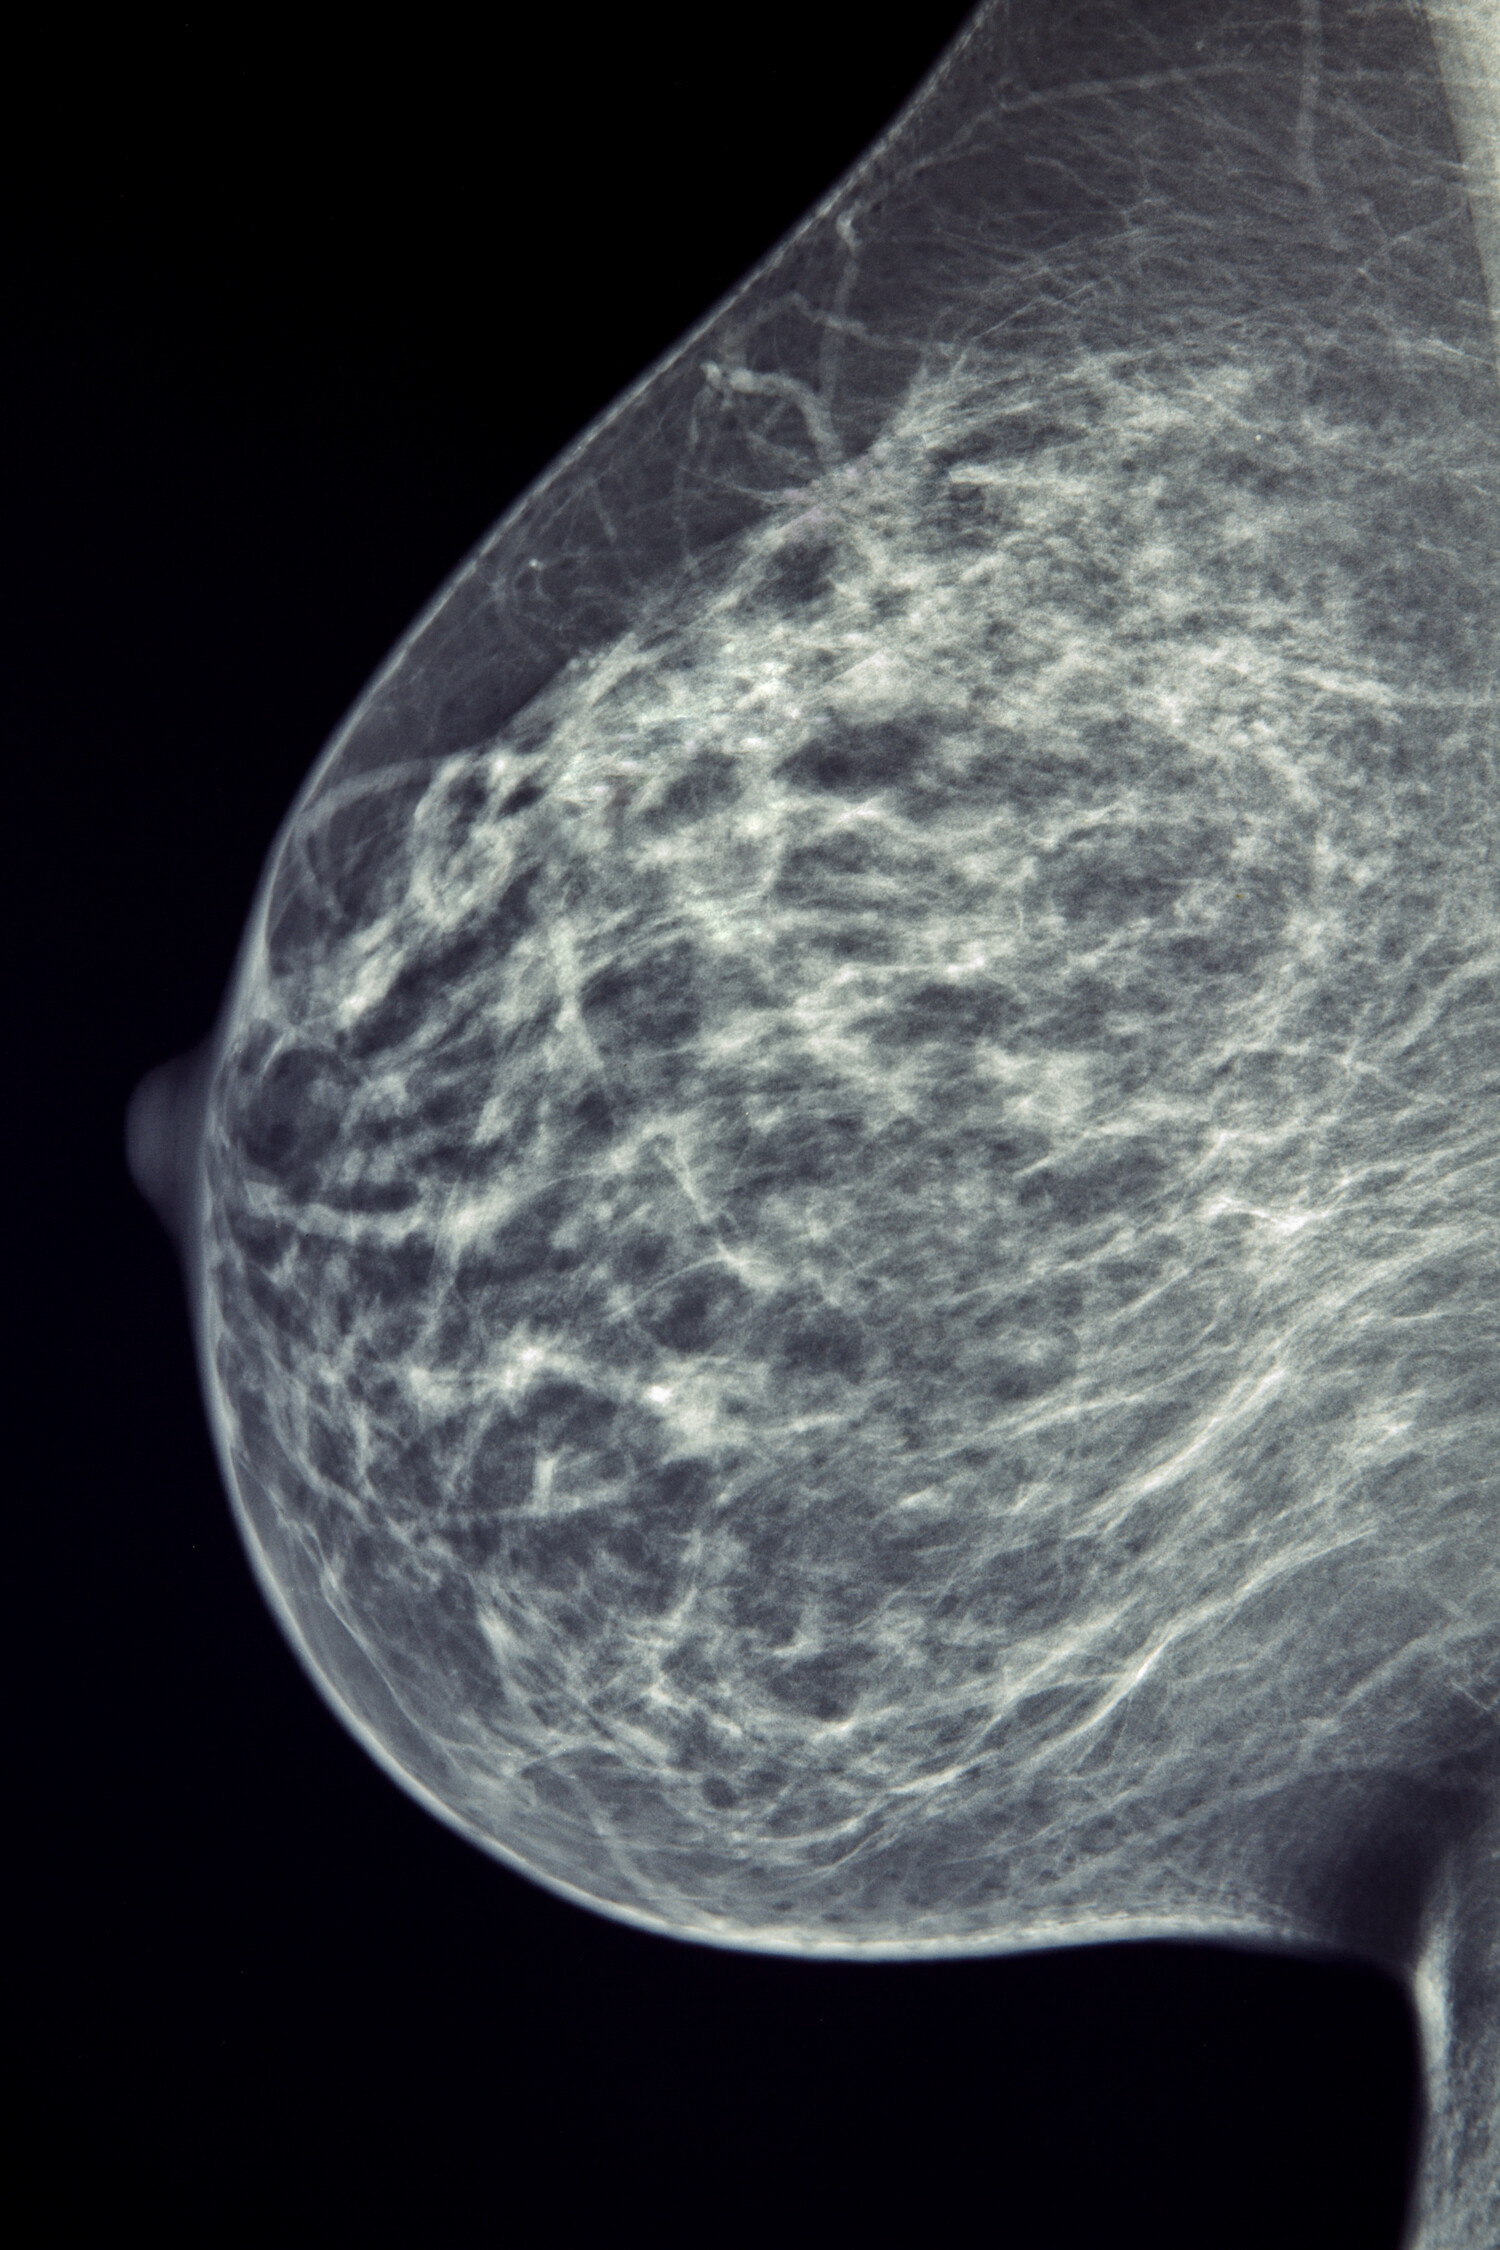

An example of a mammogram

View larger